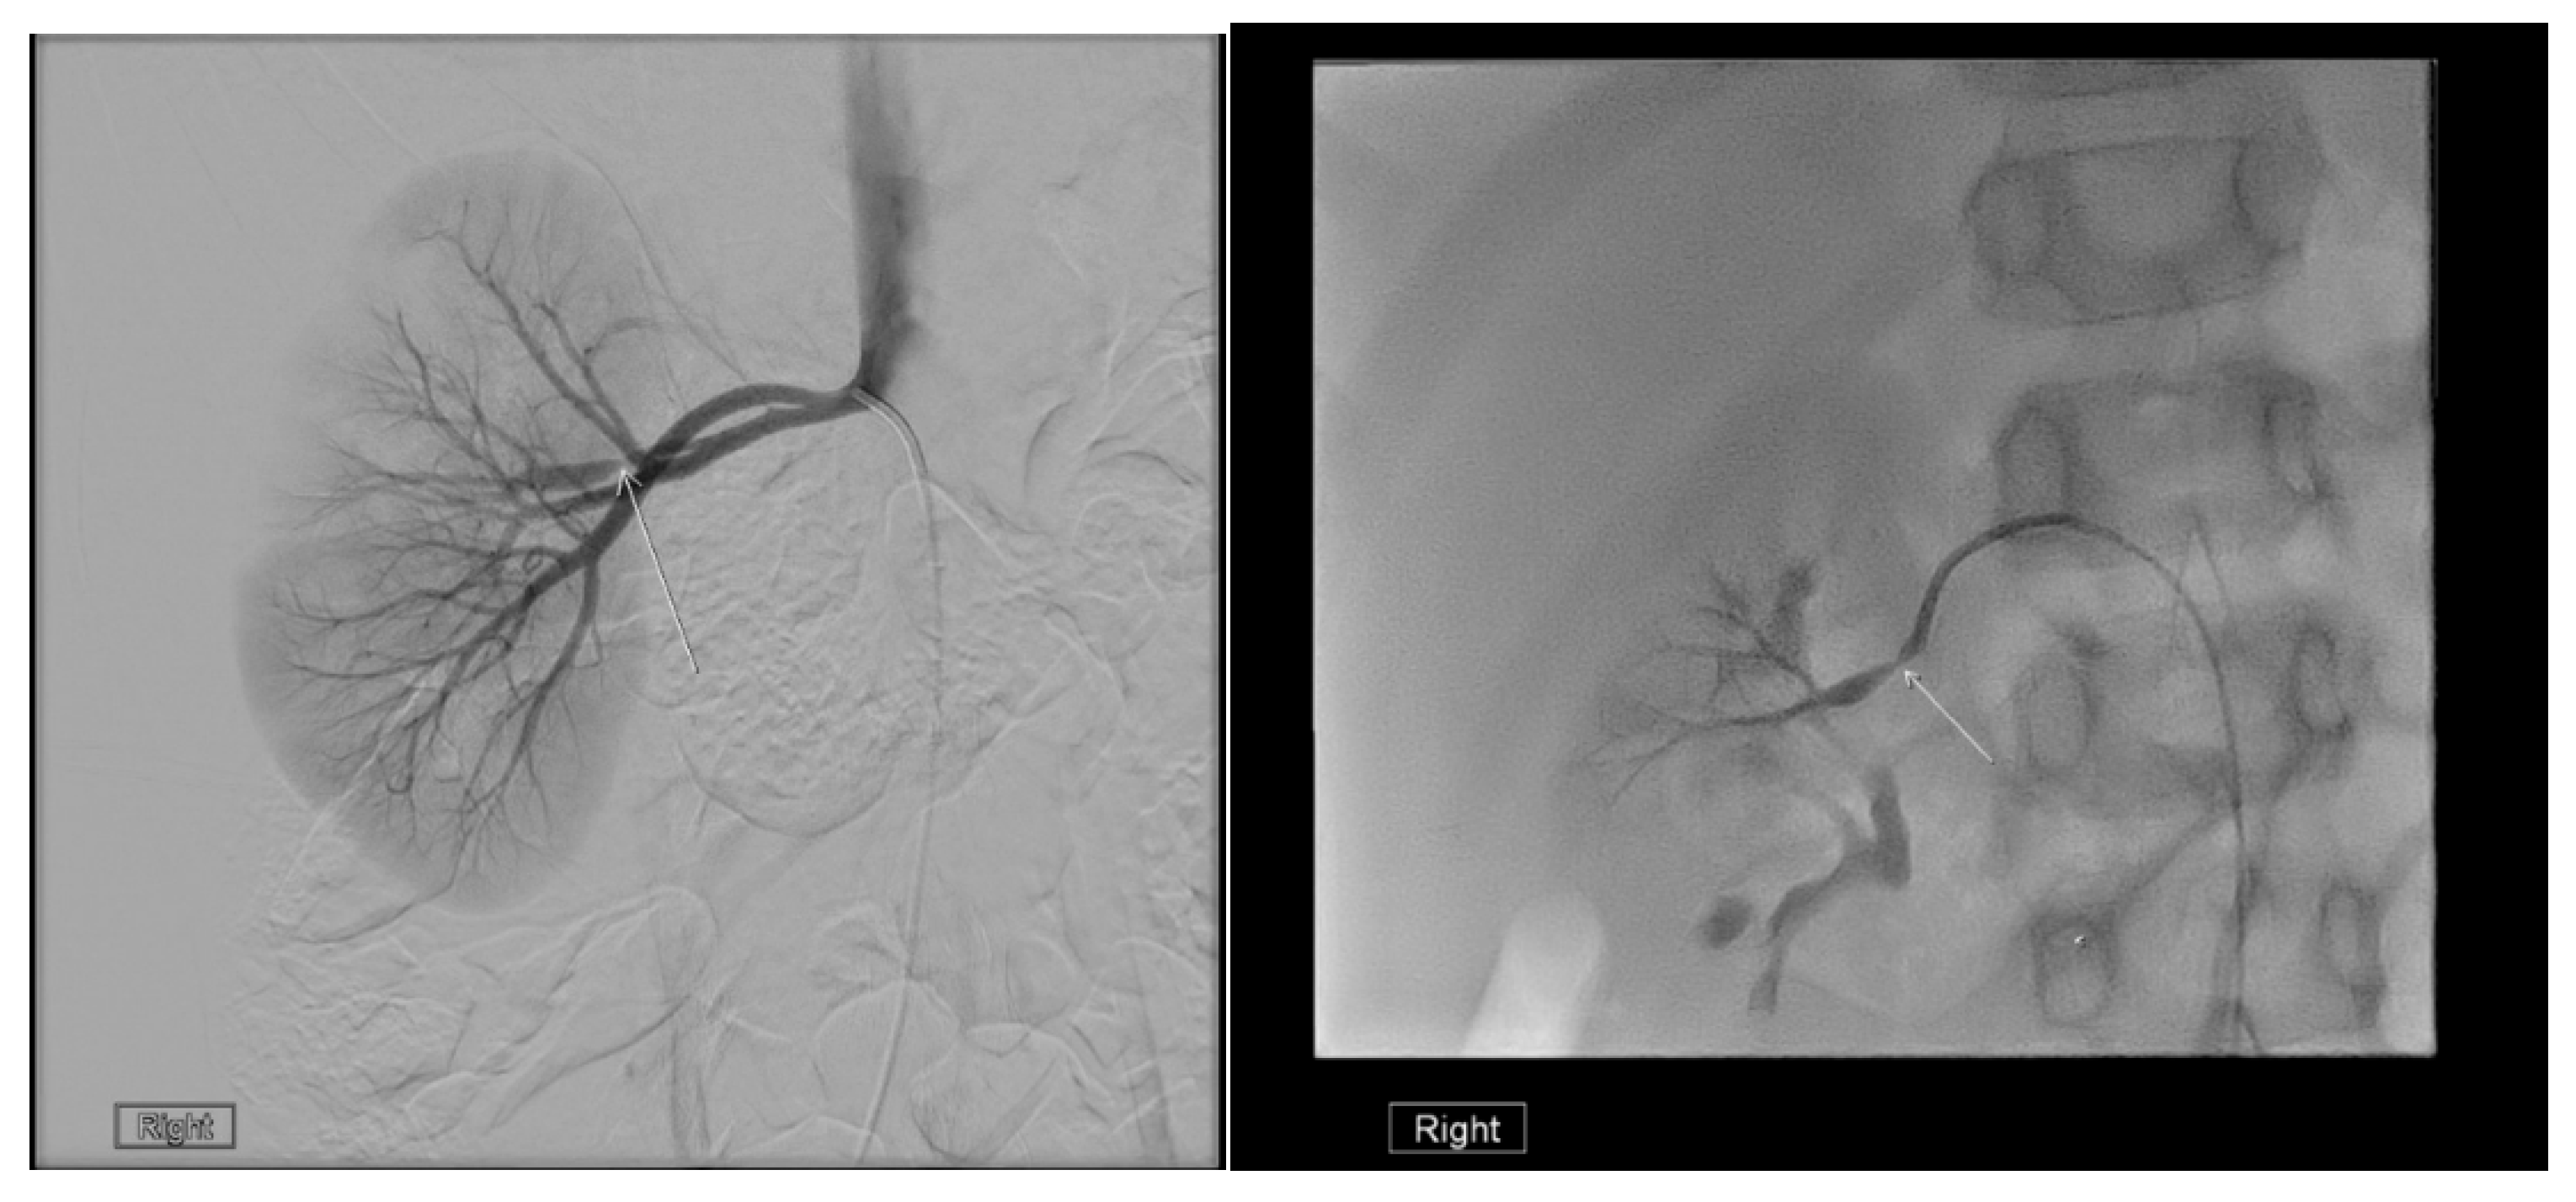

22.1. Renal Artery Stenosis